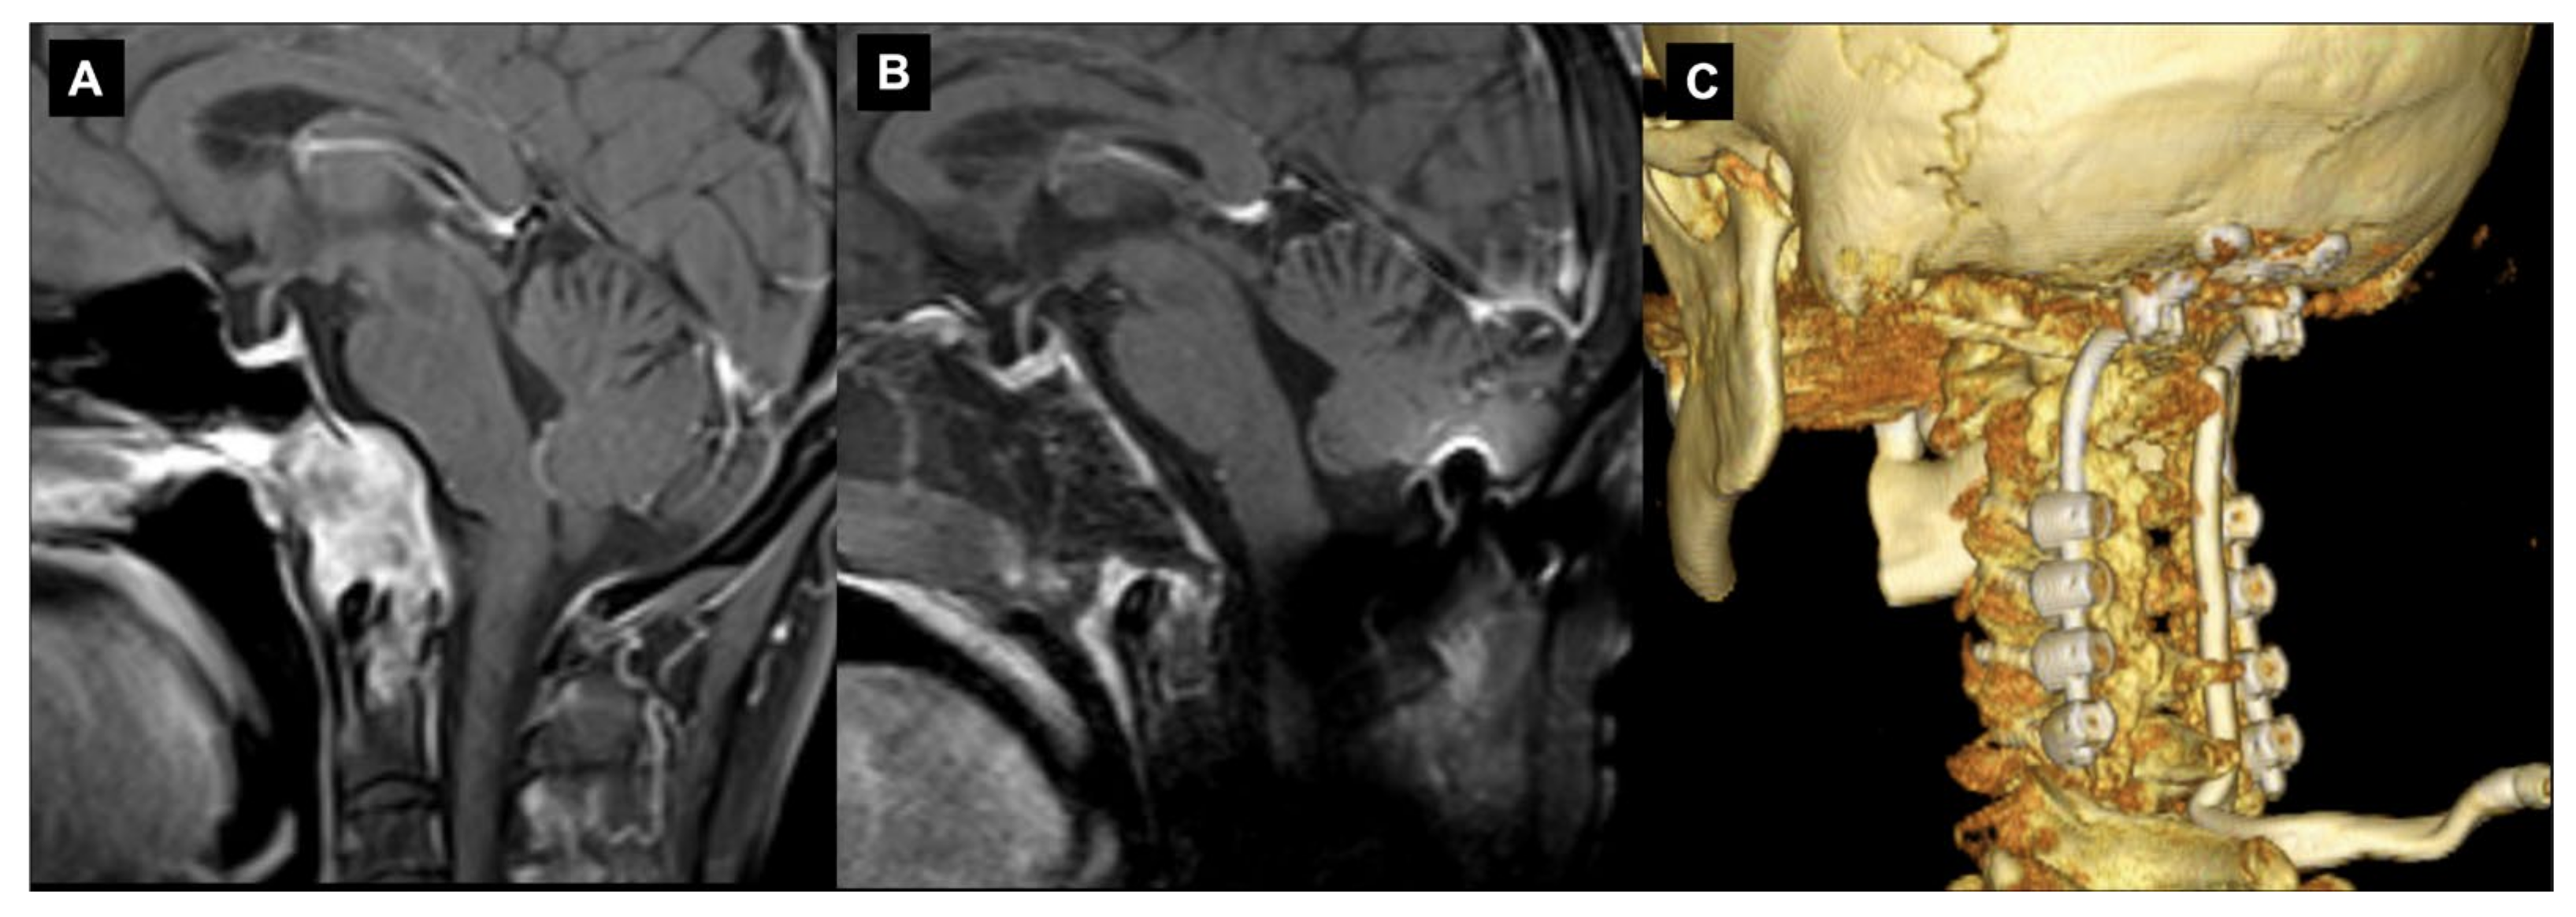

Figure 1.

Craniovertebral junction chordoma. Sagittal (A) T1-weighted image after contrast and (B) T2-weighted image depicting a large chordoma invading the rhinopharynx and extending into the premedullary cistern.

On CT, chordomas appear as well-defined expansile soft tissue masses that arise from the clivus with associated destructive lytic lesions and occasionally marginal sclerosis [43]. They appear as hypoattenuating heterogeneous lesions with areas of necrosis, hemorrhage and calcifications. Chordomas are iso/ipo-intense on T1-weighted MRI, with small hyperintense foci relative to intratumoral calcifications, hemorrhages or mucus pools. After contrast material injections, a honeycomb pattern of enhancement with intratumoral areas with a low signal intensity is typical. T2-weighed MRIs reveal a bright hyperintensity with heterogeneous hypointensities [38,44,45]. The “thumb sign” is a radiological finding that can be visible when chordomas project posteriorly at the midline and indent the pons [46].